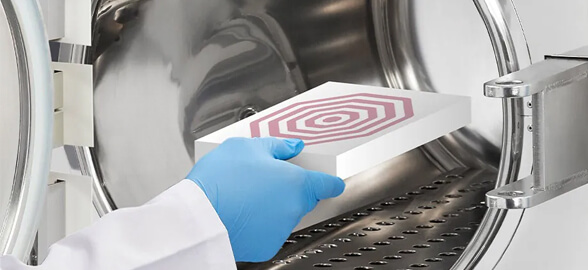

En el ámbito odontológico, la limpieza y el mantenimiento del instrumental son esenciales para garantizar la seguridad de los pacientes y la efectividad de los tra

La esterilización es uno de los procesos más importantes en una clínica dental, ya que garantiza la seguridad de los pacientes y del personal sanitario.